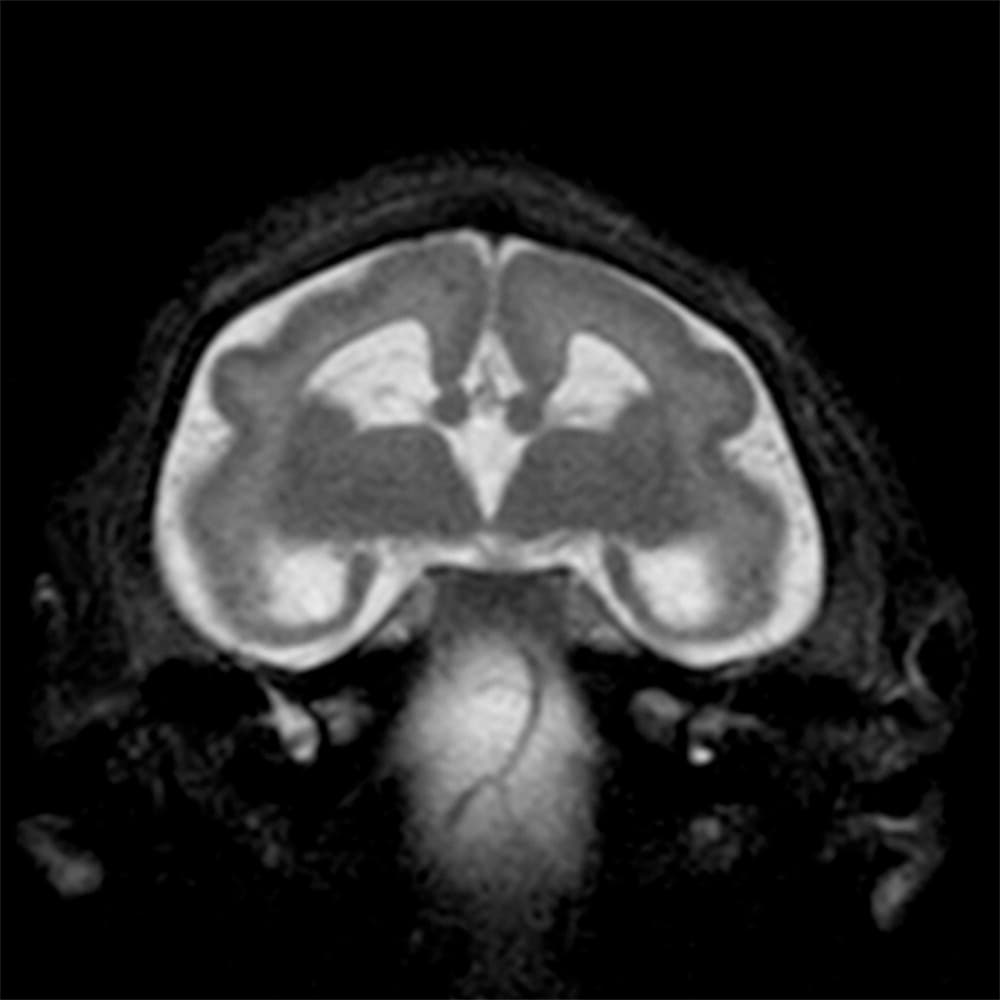

Investigadores brasileños difundieron este martes el mayor número hasta ahora disponible de imágenes computarizadas, resonancias magnéticas y ultrasonidos, de bebés y fetos infectados con el virus del Zika. El daño es mucho mayor del que anticipaban.

Así describe la radióloga brasileña Fernanda Tovar-Moll lo que vio al analizar centenares de imágenes computarizadas, resonancias magnéticas y ultrasonidos de 45 bebés que se contagiaron de zika en el vientre materno en el estado de Paraíba, en el noreste del país, donde el brote ha sido severo.

La mayoría nació con microcefalia, cuya característica más llamativa es que tienen el cerebro y la cabeza más pequeña. Pero muchos sufren una escala y severidad de daño mucho peor en partes importantes del cerebro como el cuerpo calloso, que conecta los dos hemisferios; el cerebelo, que juega un papel significativo en el movimiento, equilibrio y habla; y los ganglios basales, que controlan el pensamiento y la emoción.

Tovar-Moll es coautora de un estudio publicado el martes en la revista Radiology y fue liderado por la doctora Patricia Soares de Oliveira-Szejnfeld, a quien se le da crédito por establecer el vínculo entre el zika y la microcefalia en Brasil.